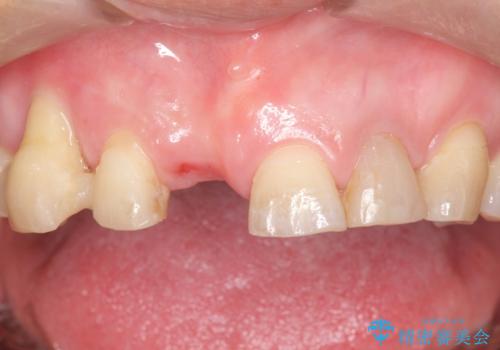

過度な咬合力 歯ぎしりで抜けた歯の欠損補綴

- 前歯を噛みしめにより失い、さらに犬歯もグラグラになり全く噛めなくなり改善を求めて来院されました。

過度な力がかかり周囲の骨に高度な吸収が見られた犬歯は抜歯し、機能・審美性の回復をより咬合力に対して抵抗力のあるブリッジ補綴にて対応します。